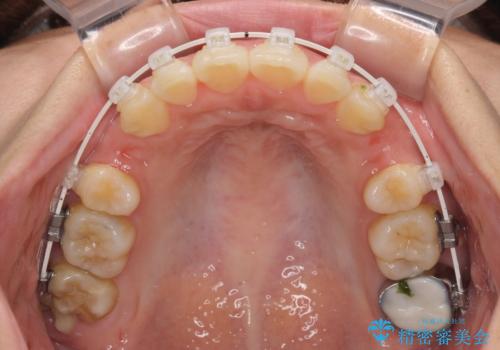

- 前歯のデコボコと口元の突出感を気にして来院された患者様です。

上下前歯がくちばしのように突出していたため、上下左右の第一小臼歯4本を抜歯し、ワイヤー装置にて矯正治療を行うこととしました。

口元の突出感が改善されてことで、下唇に引っかかっていた上顎前歯も気にならなくなりました。